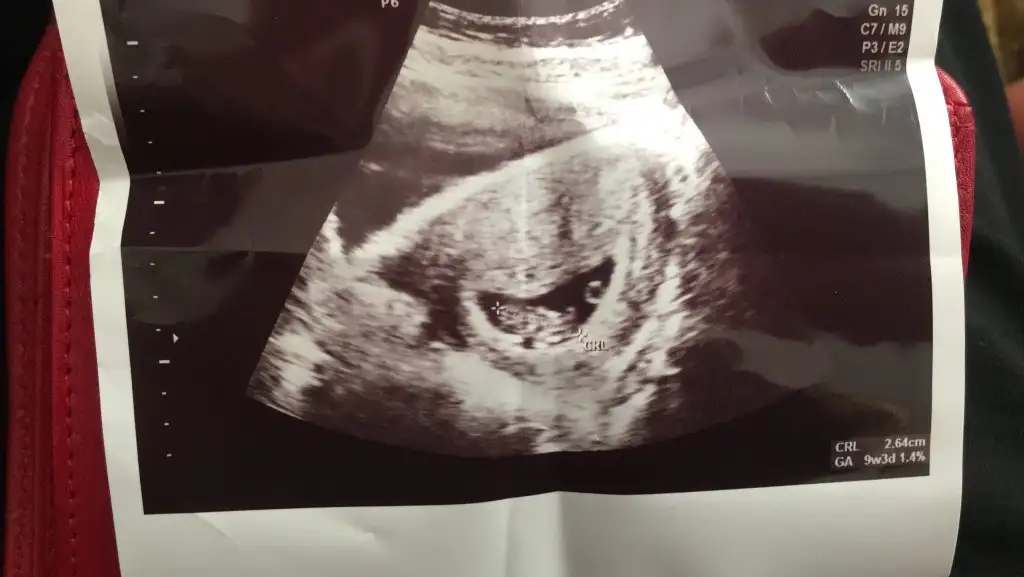

Burada 9+4 üz tahmin alabilir miyiz karından ultrason merak işte teşekkürler şimdidenErkek görünüyor![]()

Çok erken en iyi 11 12 13 haftalar olmalı şimdilik kız yönünde ama yanıltabilirBurada 9+4 üz tahmin alabilir miyiz karından ultrason merak işte teşekkürler şimdidenEki Görüntüle 2894467